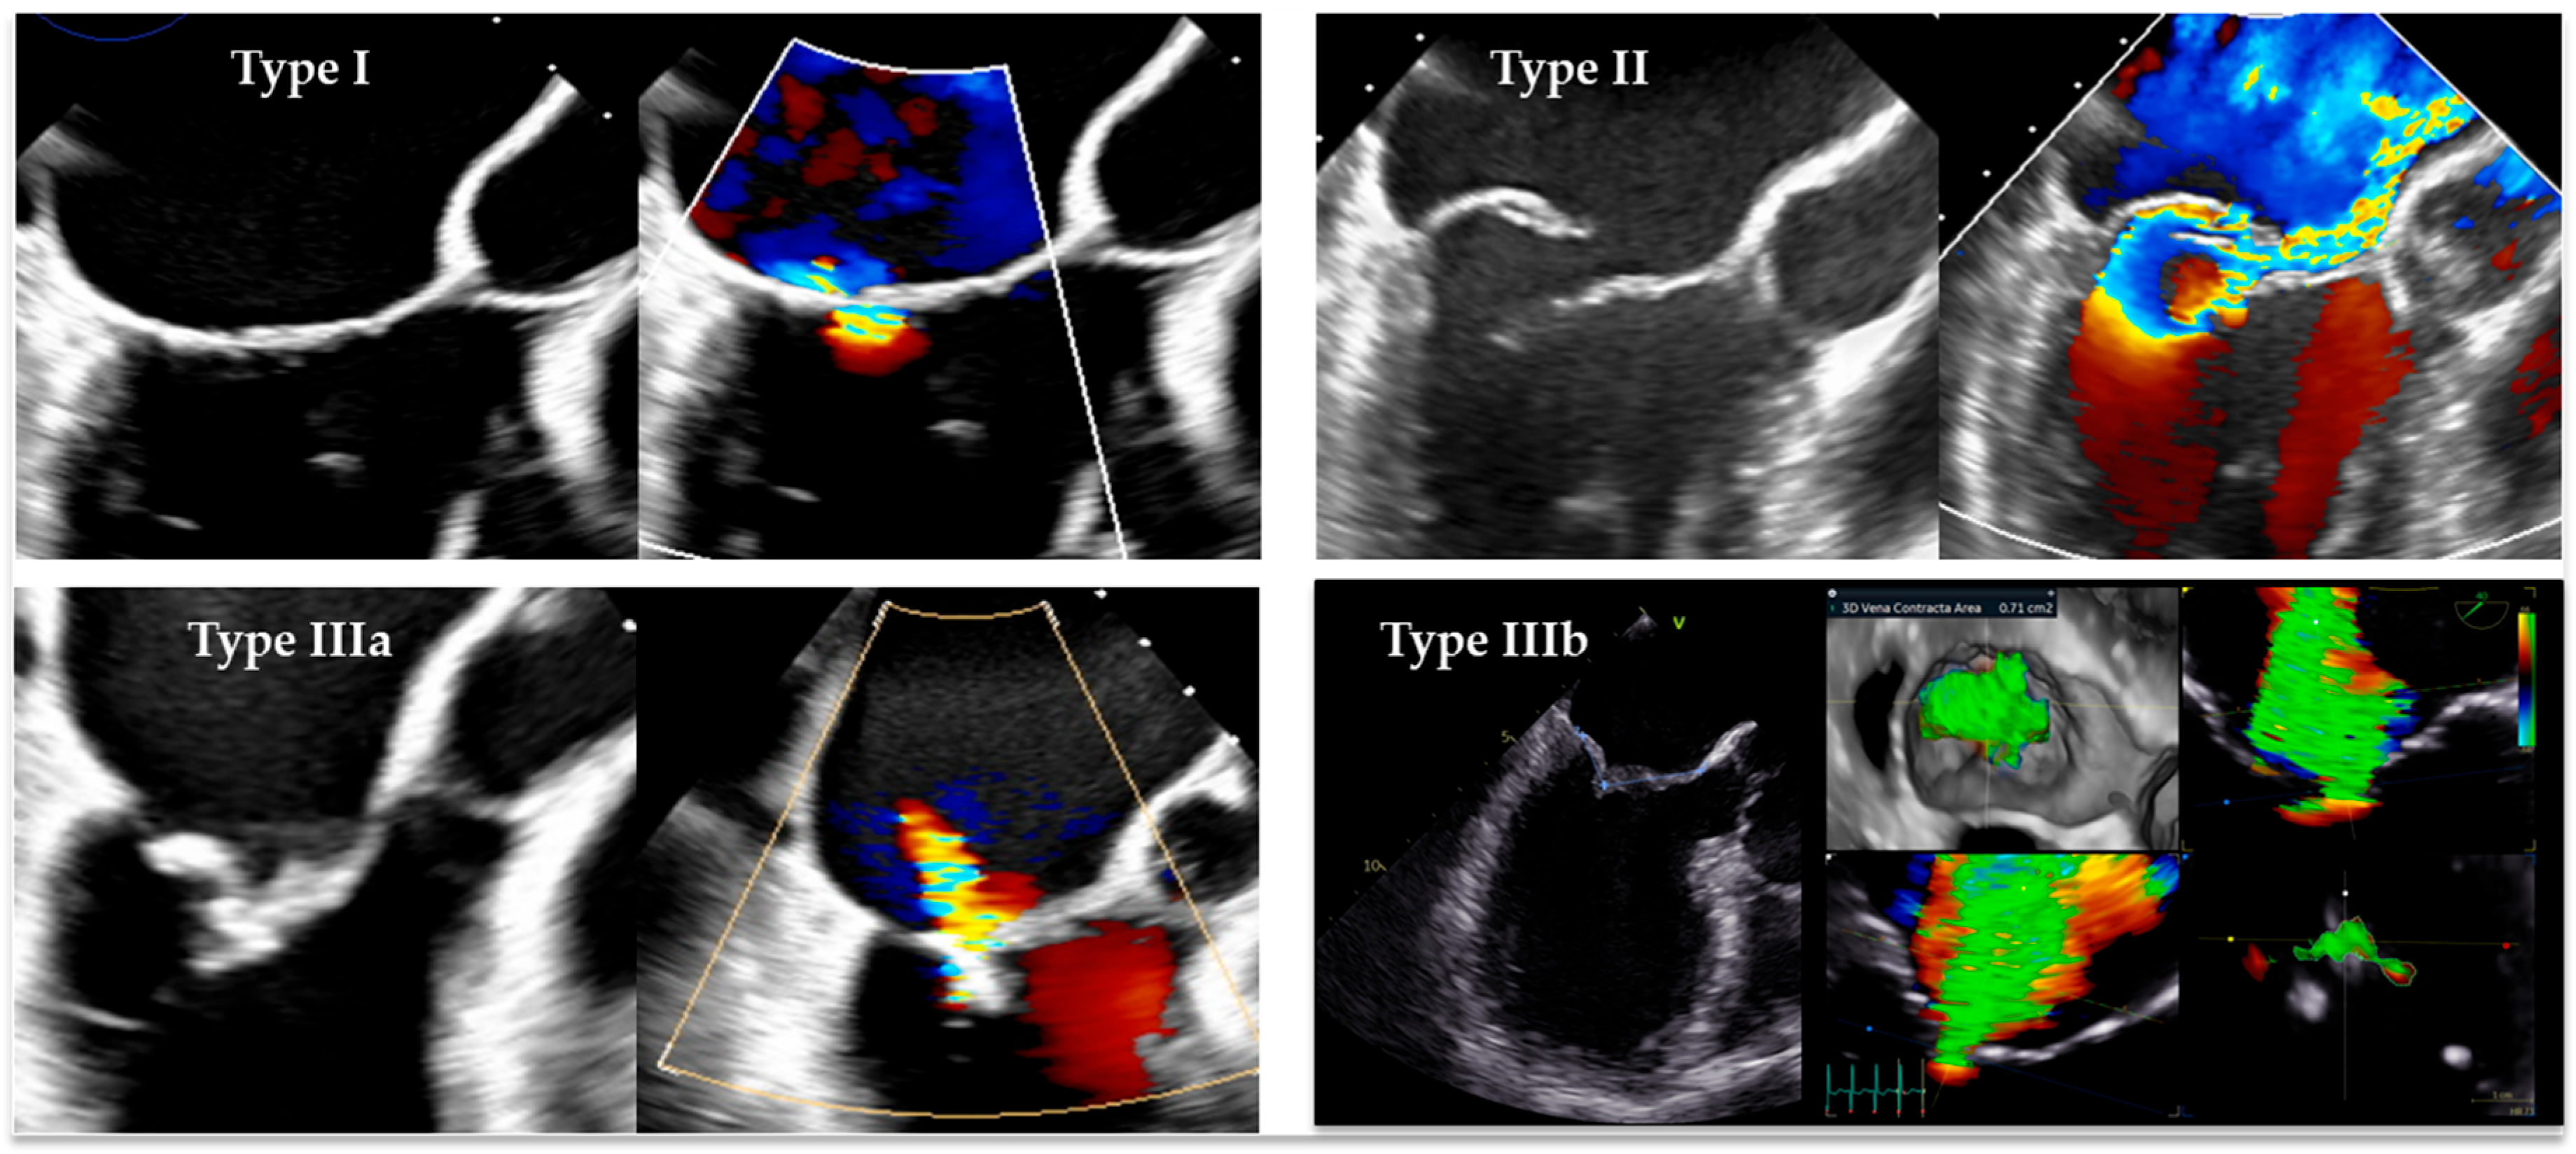

- Ventricular FMR (v-FMR): it is typically associated with ischemic or non-ischemic cardiomyopathy, where adverse LV remodeling leads to papillary muscle displacement, leaflet tethering, and annular dilatation [1].

- Atrial FMR (a-FMR): increasingly recognized as a distinct condition, it is driven by LA dilatation, atrial myopathy, and atrial fibrillation (AF), usually in the presence of preserved LV systolic function [2].

- Carpentier, A. Cardiac valve surgery-the “French correction”. J. Thorac. Cardiovasc. Surg. 1983, 86, 323–337. [Google Scholar] [CrossRef] [PubMed]